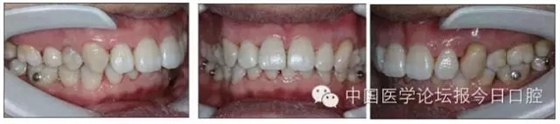

本病例為慢性牙周炎致前牙漂移、深覆(牙合)患者。本病例采用無托槽隱形矯治技術(shù)進行治療。無托槽隱形矯治器具有可摘戴、便于口腔衛(wèi)生維護和牙周治療的優(yōu)點,更適合于伴有牙周炎的錯(牙合)畸形患者的治療。 患者男,48歲,前牙有縫、前突求診。 患者面部對稱,側(cè)面觀上頜前突,下頜后縮。 口內(nèi)情況:恒牙列,24、34、44缺失,磨牙Ⅲ類關(guān)系,上牙列散隙,上前牙扇形漂移。前牙深覆(牙合)、深覆蓋??谇恍l(wèi)生較差,11與12間牙齦乳頭紅腫,多個牙探診有牙周袋形成,11松動Ⅰ度,余切牙松動(-),患者面像及口內(nèi)像如圖1、2所示。 圖1 治療前面像 圖2 治療前口內(nèi)像 全口曲面體層片(圖3)顯示,患者全牙列牙槽骨吸收;根尖片(圖4)示11近中牙槽骨角形吸收已達根尖1/3,21牙槽骨嵴頂吸收至根1/2,23牙槽骨近中骨板角形吸收至根1/2。磨牙區(qū)骨嵴頂吸收3mm。治療前頭顱側(cè)位片見圖3,治療前ODS模型見圖5。 圖4 治療前根尖片 圖5 治療前ODS模型 牙型:安氏Ⅲ類。骨型:Ⅱ類。面型:上頜前突,下頜后縮。 問題列表為:①上牙列間隙;②上切牙病理性牙移位;③前牙深覆(牙合)、深覆蓋;④24、34、44缺失;⑤慢性牙周炎。 矯治目標包括:①排齊牙列,關(guān)閉牙列間隙;②改善前牙深覆(牙合)、深覆蓋;③改善牙周狀況。 矯治設(shè)計有:①牙周基礎(chǔ)治療與維護。②壓低、內(nèi)收上切牙,關(guān)閉上牙列間隙。③壓低下切牙,伸長下后牙,整平Spee曲線,改善前牙覆(牙合)、覆蓋。 患者進行全口齦上潔治、齦下刮治,口腔衛(wèi)生宣教,并按牙周醫(yī)師的要求,每2~3個月行牙周檢查與治療。 牙周基礎(chǔ)治療結(jié)束3個月,開始隱形矯治。于14、25、35、36、45、46上粘接附件(圖6),于16、26(牙合)面粘接(牙合)墊。 圖6 ODS設(shè)計附件粘接圖示 矯治過程中注意(牙合)墊是否脫落或磨損,及時修補。 注意上前牙內(nèi)收時有無咬合干擾,及時調(diào)(牙合)。下頜前磨牙伸長到位后,磨除16、26(牙合)墊。 下頜佩戴第24步矯治器時,分別在36、37、46、47的頰、舌側(cè)粘接舌扣,矯治器上預(yù)留伸長空間,用3/16英寸、3.5盎司皮圈牽引,輔助伸長下磨牙(圖7)。 患者共戴用矯治器上頜32步,下頜26步。 矯治后,牙列間隙關(guān)閉,面型及覆(牙合)覆蓋改善。11根尖片(圖8)顯示,治療后較治療前,牙周支持組織增加,牙槽骨角形吸收區(qū)水平向縮小0.3mm,垂直向縮小0.6mm。11松動Ⅰ度,余切牙無松動。 圖8 治療后根尖片 圖9 治療后口內(nèi)像 圖10 治療后X線檢查 圖11 治療后ODS模型 正畸-牙周聯(lián)合治療對于牙周組織的影響 多學(xué)科綜合治療牙周炎患者不再是正畸治療的禁忌證。良好的牙周治療為正畸治療中的牙齒移動打下堅實基礎(chǔ),而正畸治療排齊牙齒、去除(牙合)干擾,有利于牙周健康。 牙周炎患者的正畸治療必須在牙周炎癥得到控制后才能進行,否則,菌斑會隨著牙齒的移動,特別是壓低而使牙周炎癥加重。牙周炎的正確診斷、牙周炎癥控制、正畸治療中和治療后的認真維護是治療成功的關(guān)鍵。根據(jù)臨床需要,一般每2~4周做一次潔治,每3個月進行牙周評估,同時患者必須進行非常良好的日??谇恍l(wèi)生維護。 固定矯治器使得牙周檢查、潔治和日??谇恍l(wèi)生維護變得困難,隱形矯治器可自行摘戴,便于患者日常維護和牙周治療,節(jié)約時間,提高菌斑控制效果。 有臨床研究表明,對于存在(牙合)創(chuàng)傷,伴有角形吸收的患牙,經(jīng)過牙周翻瓣手術(shù)控制住牙周炎癥后,使用正畸輕力壓低患牙,可以改善牙槽骨吸收的程度,并獲得一定程度的牙周新附著。本病例切牙壓低后,原來的牙槽骨吸收有改善。 病理性牙移位 病理性牙移位(PTM)在重度牙周炎患者中的發(fā)生率為30%~50%,且常見于上前牙區(qū)。其主要由于牙周支持組織喪失尤其是骨組織的丟失,咬合因素(如后牙缺失、前牙深覆牙合、牙合創(chuàng)傷等),頰舌唇肌力量不平衡及牙周和根尖周組織炎癥所致,是牙周炎患者要求正畸治療的主要原因之一。 PTM須通過正畸、牙周聯(lián)合,有時須配合修復(fù)才能達到理想的治療效果。正畸治療通常是壓低牙齒,臨床研究表明,牙周手術(shù)配合正畸壓低可以產(chǎn)生新附著,有利于PTM牙周組織的恢復(fù)。 本病例右上中切牙牙槽骨角形吸收,在盡量保證治療前后根尖片投照角度一致的情況下,以鄰牙作為校準,在根尖片上對治療前后的骨量進行評價,治療后牙槽骨角形吸收區(qū)水平向縮小0.3 mm,垂直向縮小0.6mm。盡管根尖片并不能說明骨量改變,但從影像學(xué)上能看到骨吸收區(qū)域有所減小。 無托槽隱形矯治器矯治牙周病的優(yōu)勢 無托槽隱形矯治器具有可摘戴、便于口腔衛(wèi)生維護和牙周治療的優(yōu)點,更適合于伴有牙周炎的錯(牙合)患者的治療;同時,無托槽隱形矯治器佩戴后具有牙弓夾板和(牙合)板的作用,可有效減少側(cè)向力,有利于牙周的恢復(fù)和減輕牙齒松動;由于無托槽隱形矯治器的設(shè)計是在三維數(shù)字模型上進行的,每個矯治器移動牙齒的數(shù)量和每個牙齒的移動距離可以得到量化控制,因而可以根據(jù)患者牙槽骨水平和對矯治力的耐受情況個性化設(shè)計矯治力,并且可以根據(jù)矯治中牙齒移動情況調(diào)整后續(xù)矯治器的設(shè)計。 有關(guān)磨牙伸長 單純使用無托槽隱形矯治器同步伸長后牙比較困難。該病例先使用磨牙(牙合)墊打開咬合,通過矯治器伸長前磨牙,在前磨牙建立咬合后,磨除磨牙上的(牙合)墊,通過輔助牽引伸長磨牙,最終達到伸長后牙、整平Spee曲線的目的。 史真,主任醫(yī)師,現(xiàn)任北京黃寺整形外科醫(yī)院口腔科主任,第四軍醫(yī)大學(xué)口腔正畸學(xué)碩士,為世界正畸醫(yī)師聯(lián)盟(WFO)會員、全軍口腔醫(yī)學(xué)專業(yè)委員會委員、中華口腔正畸專業(yè)委員會委員、中華醫(yī)學(xué)美學(xué)與美容學(xué)會齒科美容學(xué)組成員、北京口腔醫(yī)學(xué)會兒童口腔專業(yè)委員會常務(wù)委員、北京口腔醫(yī)學(xué)會正畸專業(yè)委員會委員、《中華醫(yī)學(xué)美學(xué)與美容》雜志審稿專家,是我國最早開展無托槽隱形矯治技術(shù)的口腔醫(yī)師之一。